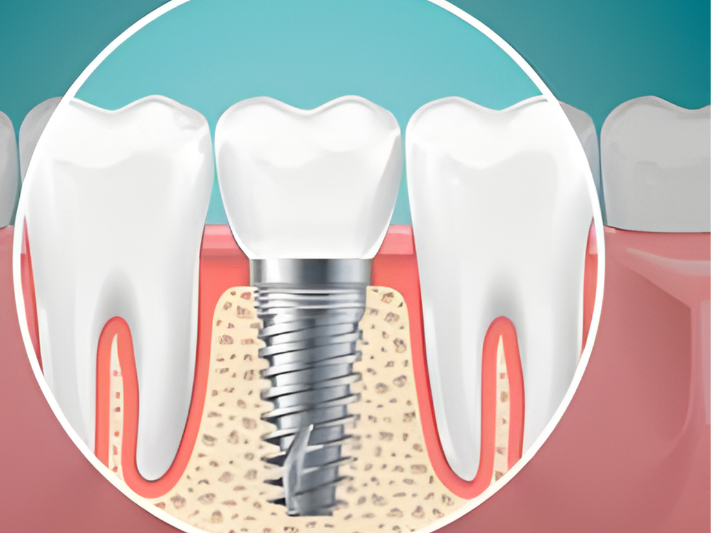

Dental Implants

Replace missing teeth with strong, natural-looking implants that restore full chewing ability and maintain long-term oral health.

Dental Implants